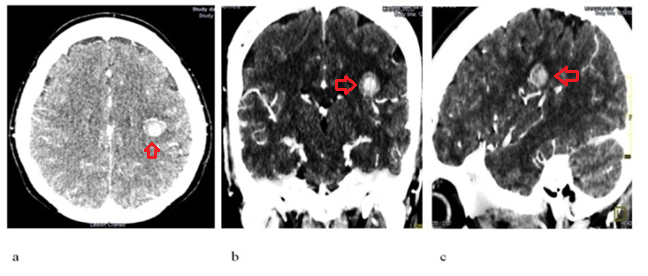

A non-contrast and subsequent intravenous contrast-enhanced axial computed tomography scan of the head was carried out. It revealed a hyperdense, rounded lesion with a whorled appearance and a density of 54 HU, located in the left parietal lobe (Figure 1 a, b, c). A CT angiography of the head showed a hyperdense (54 HU), rounded, whorled-appearing lesion located in the left parietal lobe within the territory of the middle cerebral artery, with drainage into the inferior sagittal sinus (Figure 2).

Fig. 1 - CT scan of the head without and with contrast: a (axial view), b (coronal view), c (sagittal view). The previously described rounded, white (hyperdense) image is indicated with a red arrow.